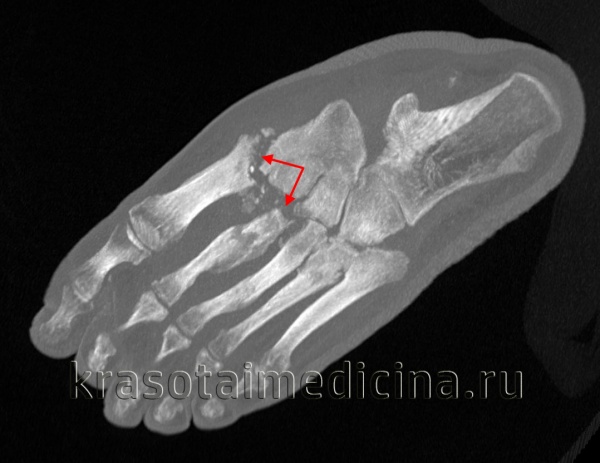

КТ стопы. Деструкция сустава Лисфранка на фоне длительно существующего хронического гнойного артрита посттравматического характера.